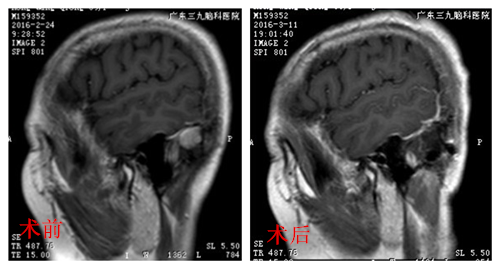

为了进一步确诊,儿子带着洪阿姨来到广东三九脑科医院神经外三科,行头颅MRI+增强提示:左侧小脑幕脑膜瘤,肿瘤位于可切除部位。由杨宝应医生主刀,在全麻下为洪阿姨进行肿瘤切除手术,术程顺利。洪阿姨麻醉清醒后,恢复良好,也没有出现功能神经损害症状,已康复出院。术后病理结果提示脑膜瘤 (WHO I级)。